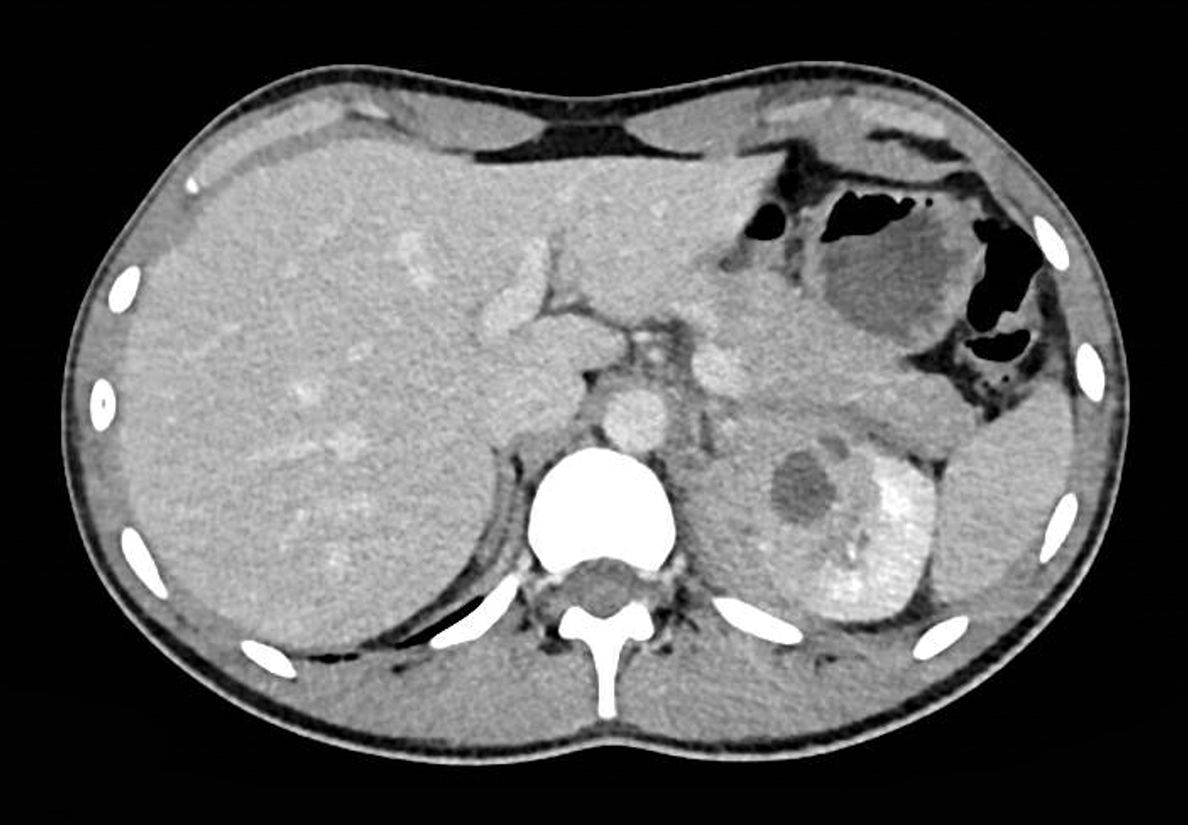

Un homme de 20 ans, sous immunosuppresseurs, est hospitalisé pour une douleur lombaire gauche et de la fièvre. La protéine C réactive (CRP) est à 150 mg/l. L’examen cytobactériologique des urines (ECBU) est stérile.

Le scanner montre  une image hypoactive bien limitée témoignant d’un abcès rénal. L’examen cytobactériologique des urines (ECBU) étant stérile et le malade restant fébrile sous céphalosporines de troisième génération, une biopsie rénale est effectuée mettant en évidence un staphylocoque. Un traitement par sulfaméthoxazole est instauré permettant d’obtenir l’apyrexie.